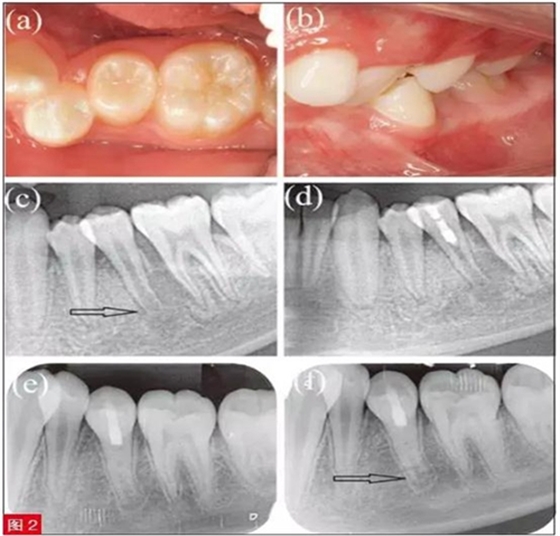

患者為11 歲男童,主訴左下后牙疼痛腫脹3天,近日出現(xiàn)多次陣發(fā)痛,故前來(lái)就診。臨床檢查,見(jiàn)左下第二前磨牙畸形中央尖折斷。35 牙冷測(cè)和EPT 測(cè)試均無(wú)反應(yīng),而鄰牙34、36 反應(yīng)正常。35 叩診(+),I度松動(dòng),頰側(cè)根尖區(qū)牙齦隆起伴壓痛,牙周探診正常。根尖片示35 牙根未發(fā)育完全,根尖孔敞開(kāi)且根尖周有明顯透射影(圖2c)。

對(duì)35 進(jìn)行臨床和影像檢查,初步診斷為有癥狀的根尖周炎。面開(kāi)髓后,可觀察到根管中段近冠方處有粉色、質(zhì)地連續(xù)的活髓組織,最終診斷為35 牙部分牙髓壞死伴有癥狀的根尖周炎。隨即對(duì)該患牙進(jìn)行部分牙髓切斷術(shù)。治療過(guò)程與病例1 相仿(圖2d)。

患者6 個(gè)月后隨訪,根尖片示35 根尖周透射影完全消失(圖2e)。8 個(gè)月后復(fù)查,患者癥狀完全消除,偶遇熱水會(huì)出現(xiàn)一過(guò)性敏感。根尖片示根尖周組織愈合,牙根長(zhǎng)度和根管壁厚度均明顯增加(圖2f),且無(wú)任何臨床癥狀和體征(圖2a 和2b)。患牙冷測(cè)和EPT測(cè)試均顯示牙髓有活力,其中EPT 值為31,與鄰牙36的EPT 值21 相近。